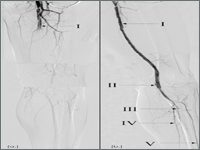

Wewnątrznaczyniowe leczenie ostrego niedokrwienia kończyn dolnych - opis przypadku

Endovascular treatment of acute limb ischemia - a case report

SurgeryAcute ischemia is a sudden drop in blood perfusion in a limb causing a potential threat to the viability of the limb. The 30-day amputation rate due to acute ischemia is 10% to 30%, with a mortality rate of 15-20%. For several years, in addition to surgical methods, we have had the option of endovascular treatment of of acute ischemia. The methods used: targeted pharmacological thrombolysis, percutaneous aspiration thrombectomy, percutaneous mechanical thrombectomy and various combinations of these procedures.